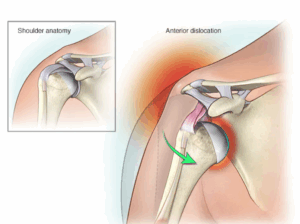

Shoulder dislocation

A dislocated shoulder is an injury in which the upper arm bone pops out of the cup-shaped socket that's part of the shoulder blade. The shoulder is the body's most flexible joint, which makes it more likely to dislocate.